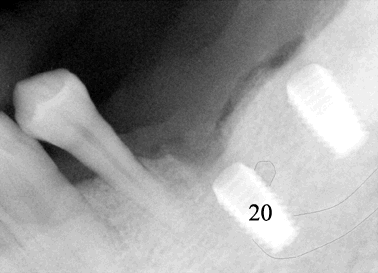

Fig.20 and 21 These two X-ray images were taken immediately after pressing in a 4.5x8 Bicon implant. Before implant insertion, surgical curet was used to remove bone shaving from osteotomy site and gently explore the wall of the osteotomy next to the mental nerve. It was felt that there is no perforation. The patient reported minimal numbness post-op. Exposure and stretching the mental nerve during procedure may contribute to this type of minor nerve injury. Retrospectively, the implant could have been smaller in diameter: 4.0 or 3.5 mm. Restoratively these two implants should be splinted due to the angulation discrepancy. |